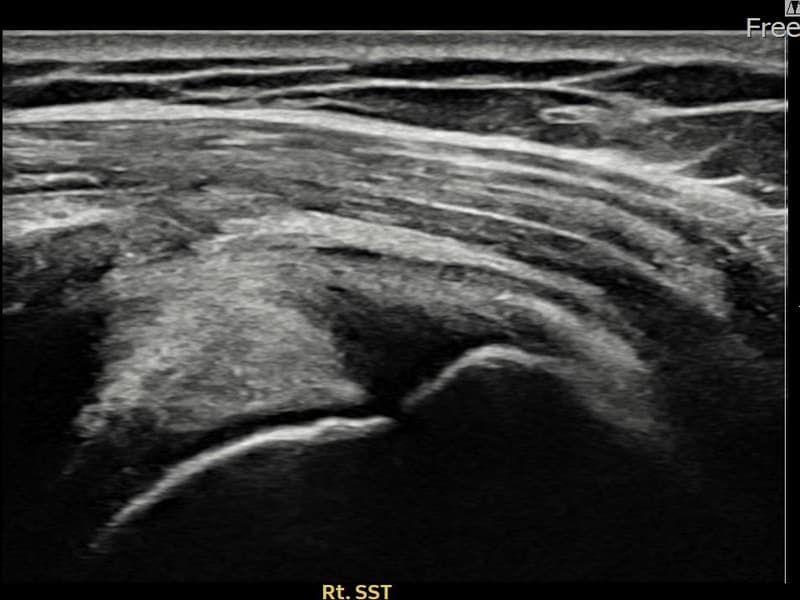

施術前

術前超音波にて右 棘上筋腱 滑液包面側部分断裂・右肩棘上筋腱のエコー不連続と腱欠損(8mm × 4mm (腱厚の約35%欠損))を確認。術後超音波では断裂部位が再生組織で充填され、腱の連続性回復とエコーパターンの正常化が確認されました。